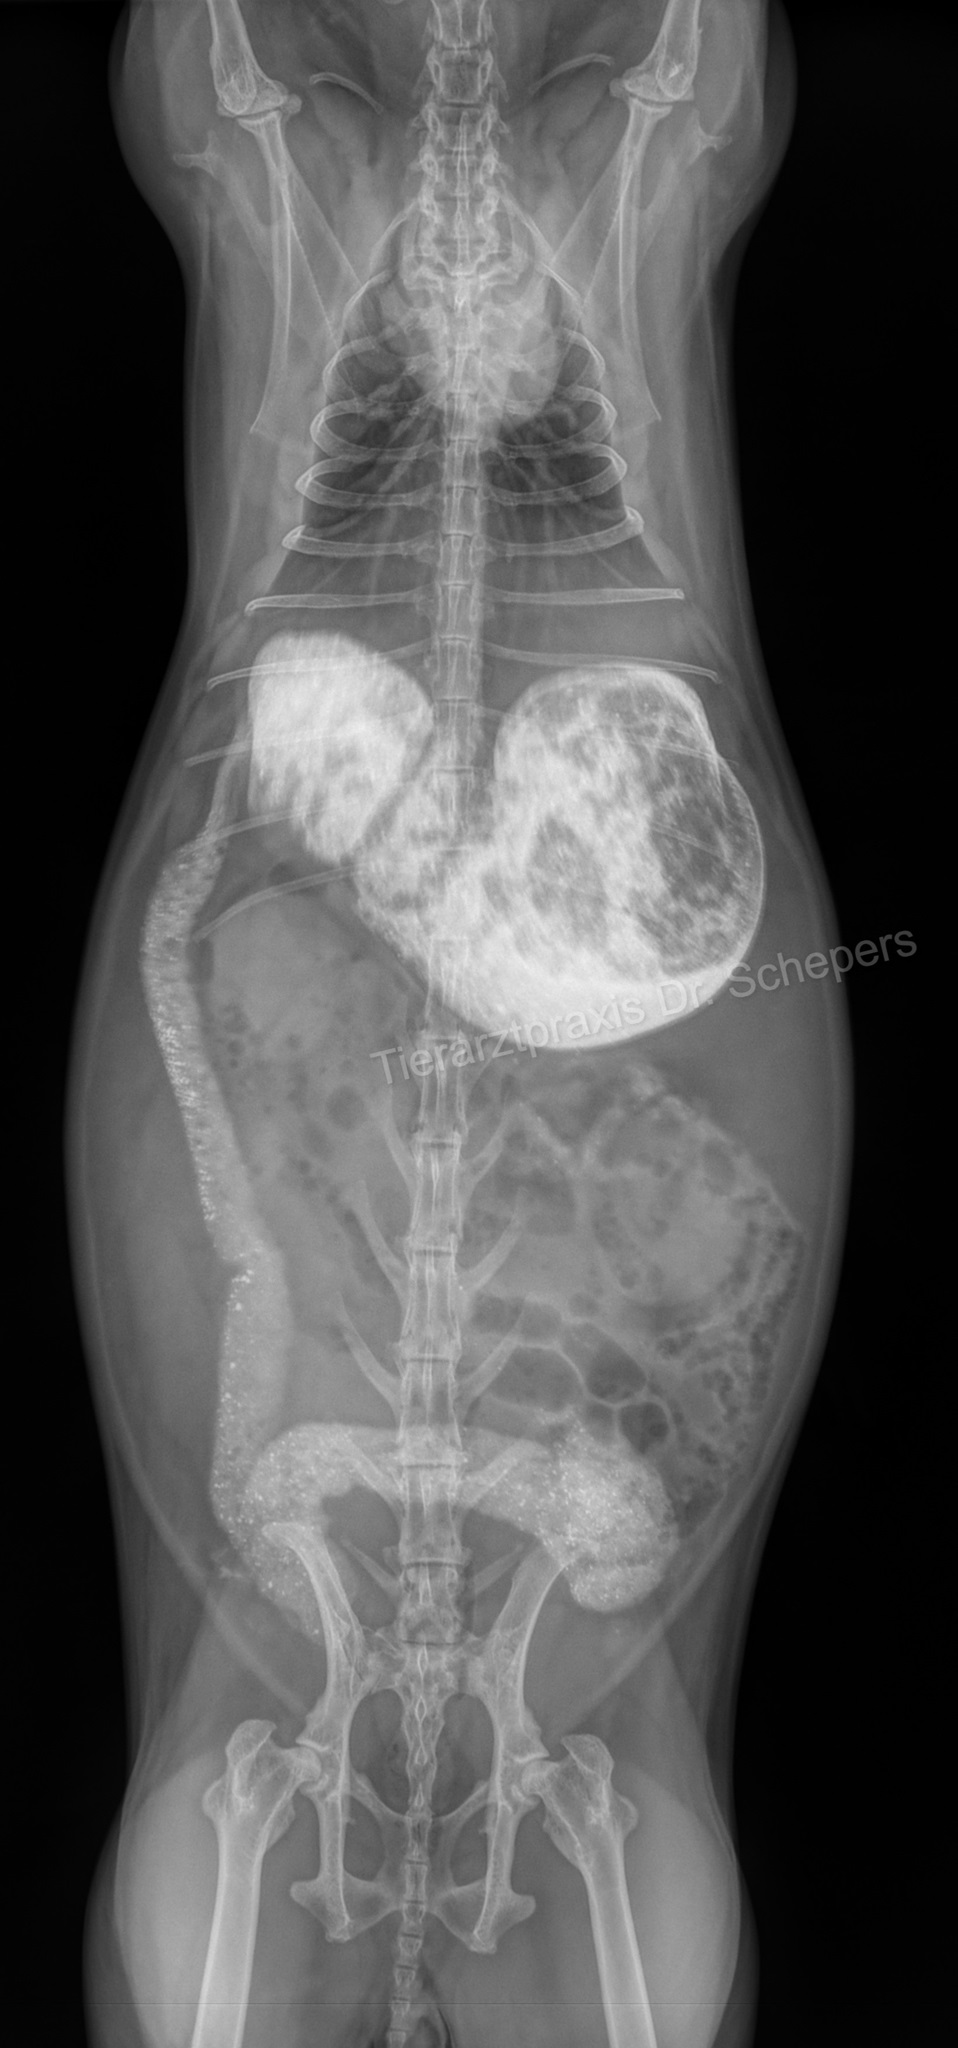

Röntgendiagnostik

Die sichere Diagnose wird durch ein Röntgenaufnahmen gestellt; hierdurch kann die Konsistenz des Mageninhalts (fest, flüssig, aufgegast) auch von weniger geübten Tierärzten sicher und objektiv beurteilt werden. Zudem besteht eine objektive Vergleichsmöglichkeit für spätere Verlaufskontrollen.

Die genaue Diagnose ist elementar für die anschließende Therapie:

• leerer Magen-Darm-Trakt, geschwächte Magen-Darm-Motorik, leichte Verstopfung => Zwangsfütterung notwendig

• Verschluss (mechanischer Ileus) oder massiv überfüllter Magen => Zwangsfütterung fatal!

Weiterhin kann objektiv beurteilt werden, wie groß der Magen tatsächlich ist, wie lange der Zustand bereits besteht (beim mechanischen Ileus v. a. anhand der Konsistenz des Mageninhaltes: anfangs homogen, anschließend "spiegeleiartig" durch beginnende Gasbildung) sowie inwieweit eine Magentympanie (= Aufgasung) beteiligt ist. Ein gewöhnlicher Kaninchenmagen ist rund, mit homogenem, strukturiertem Inhalt gefüllt und ragt maximal zu einem Drittel über den Rippenbogen hinaus.

Auch kann die Füllung des Magen-Darm-Trakts bereits einen deutlichen Hinweis auf einen Darmverschluss liefern: Bei dem typischen, im vorderen Dünndarmbereich lokalisierten Verschluss ist die Darmschlinge unmittelbar hinter dem Magenausgang leer und luftgefüllt, der dahinter befindliche Darm hingegen noch futtergefüllt.

Sitzt der Verschluss in einem anderen Darmabschnitt, kann der Darm zu größeren Anteilen mit Luft gefüllt sein oder gefüllte, stark dilatierte (= überdehnte) Areale aufweisen. In letzterem Fall kann der Magen (noch) eine normale Größe besitzen, da sich der Futterbrei zunächst im Dünndarm und erst später bis in den Magen zurückstaut.

Angeschoppte Köttel im Enddarm deuten auf eine dort befindliche Verstopfung hin.

Kontraströntgen

Insbesondere empfiehlt sich ein Kontraströntgen, um zwischen einem kompletten Darmverschluss und einer "nur" verlangsamten / erschwerten Darmpassage unterscheiden zu können, einen möglichen Verschluss genau zu lokalisieren (Grenze von Kontrastmittel zu Gas, Dicke der Darmschlingen) sowie Magenbezoare zu identifizieren.

Hierfür wird dem Kaninchen vom Tierarzt ein Kontrastmittel (Bariumsulfat oder eine jodhaltige Substanz) eingegeben, das erste Kontrollröntgen erfolgt nach 20-30 Minuten. Dabei kann beobachtet werden, ob und wie schnell sich das Kontrastmittel (und somit der Nahrungsbrei) durch den Magen-Darm-Trakt bewegt.

Nach 20-25 Minuten sollte das Kontrastmittel bereits deutlich sichtbar in den Dünndarm übergetreten sein. Nach spätestens 60 Minuten sollte es auch im Caecum sichtbar sein, nach 3-5 Stunden sollte es den kompletten Darm passiert haben.

Magenbezoare fallen dadurch auf, dass sie sich nicht mit dem Kontrastmittel anreichern. Stattdessen wird ein ausgesparter Bereich sichtbar. Die Übergänge zum kontrastmittelgefüllten Bereich sind meist fransig. In einem Magen, der frei von Haarballen ist, verteilt sich das Kontrastmittel hingegen vollständig und legt sich glatt den Magenwänden an.